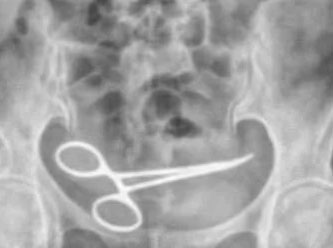

Ankara'da tedavi gördüğü özel hastanede yapılan ameliyattan yaklaşık 8 ay sonra şiddetli karın ağrısı şikayetiyle başka bir hastaneye başvuran Şadiye Boyun’un (54) çekilen röntgeninde karın bölgesinde ameliyat makası olduğu ortaya çıktı. Ameliyat sırasında unutulduğu belirlenen makas, yine ameliyatla alındı. Boyun, ameliyatı gerçekleştiren doktor ve hastane hakkında suç duyurusunda bulundu.

Ankara'da Şadiye Boyun, 28 Aralık 2021 tarihinde Pursaklar ilçesinde, özel hastanede bir kadın hastalığı nedeni ile ameliyat oldu. Ameliyattan 8 ay sonra karın ağrısı şikayeti görülen Boyun, ambulans ile Pursaklar Devlet Hastanesi'ne kaldırıldı. Burada çekilen röntgende Boyun'un ince bağırsağına takılı 12 santim boyunda makas olduğu görüldü. Ardından iddiaya göre, ameliyatın gerçekleştirdiği özel hastaneye haber verildi. Özel hastaneden görevliler geldi.

Görevliler tarafından tekrar özel hastaneye götürülen Boyun’un röntgeni çekildi. Bunun üzerine oğlu Fatih Boyun, durumdan şüphelenerek e-Nabız uygulamasından röntgen sonuçlarına baktı ve annesini Gülhane Eğitim ve Araştırma Hastanesi'ne sevk ettirdi. Şadiye Boyun'un karnındaki makas ameliyatla alındı. Boyun, avukatı aracığıyla, ameliyatı gerçekleştiren doktor ve hastane hakkında suç duyurusunda bulundu.